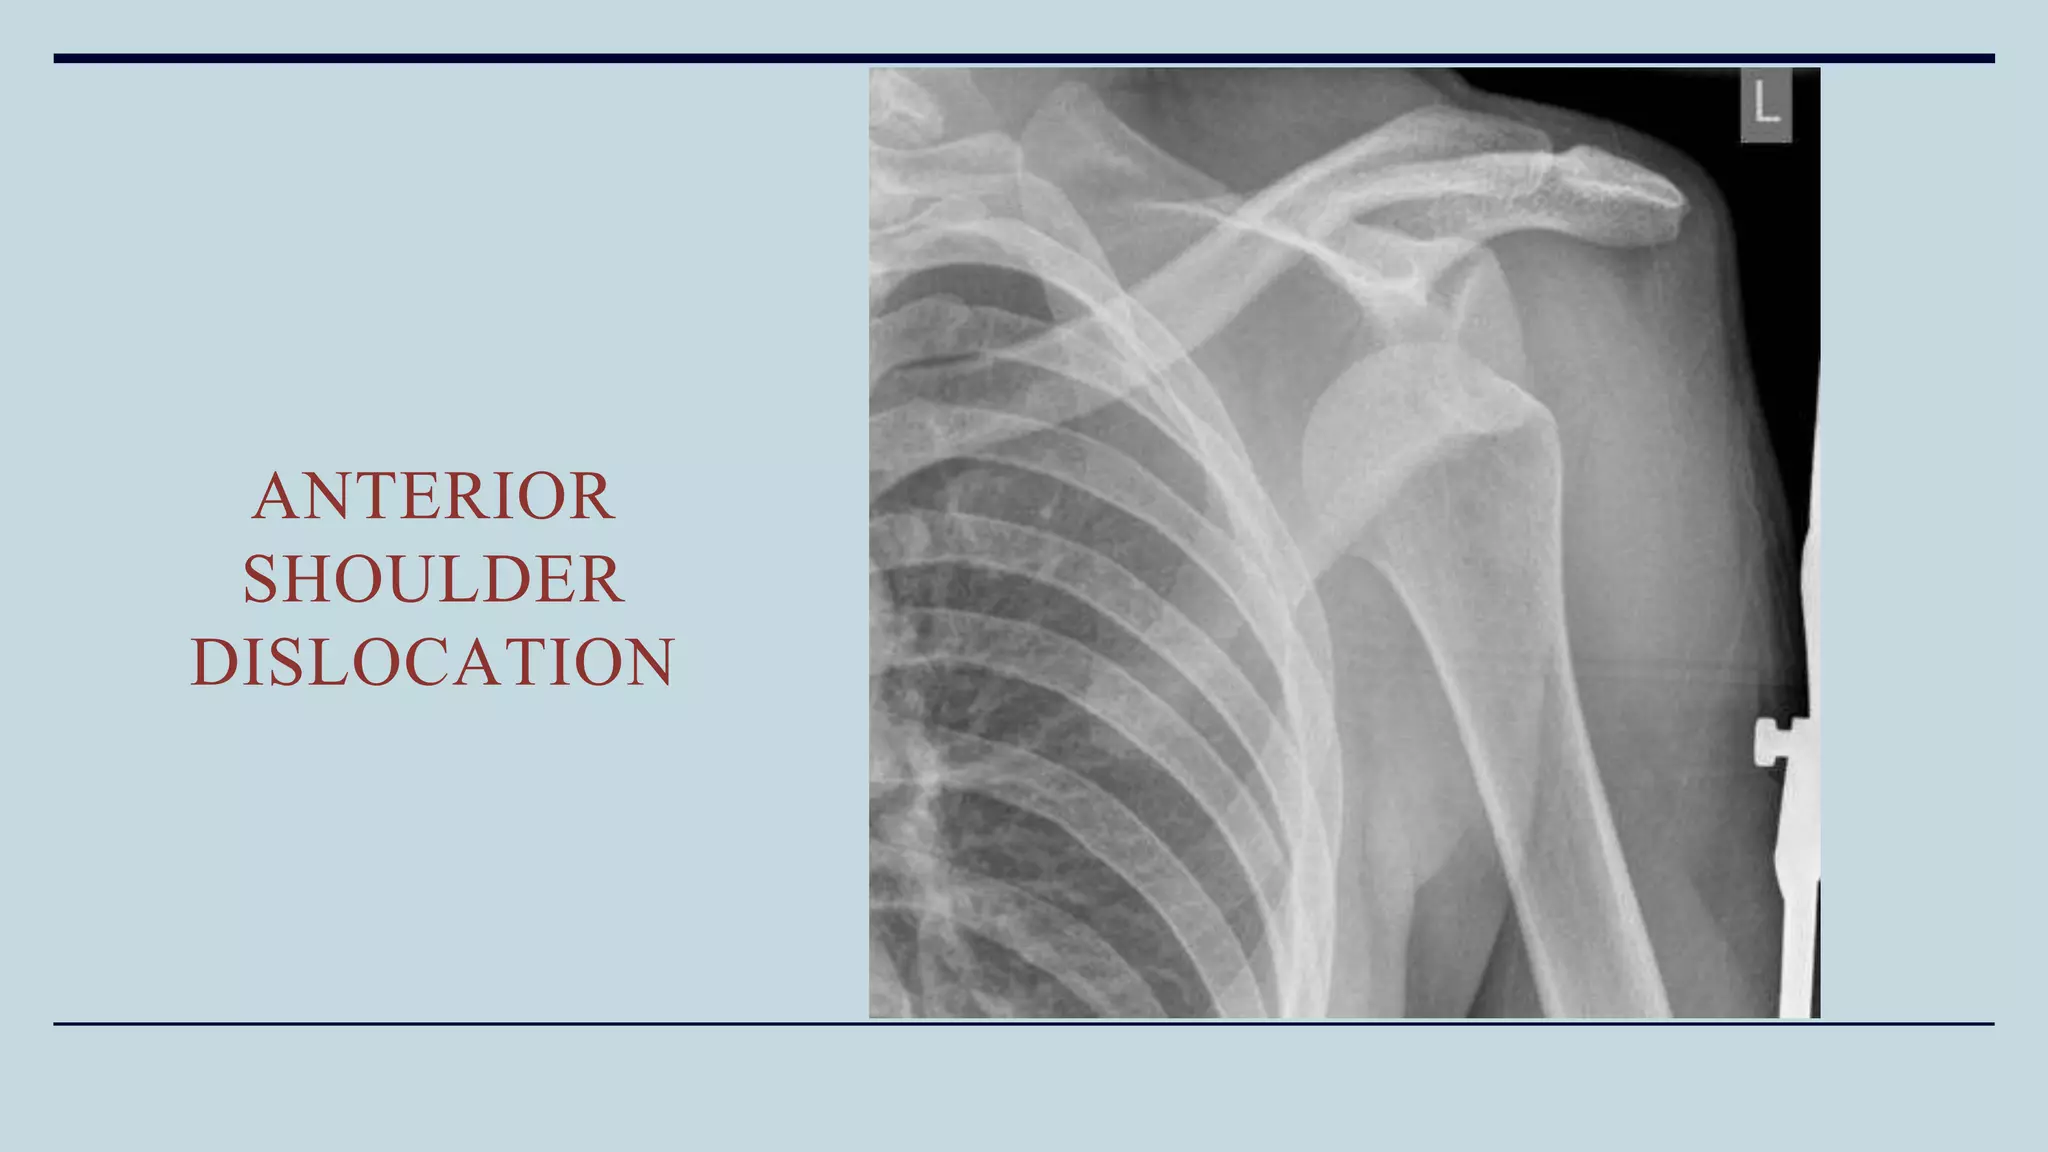

Radiographic Evaluation

• True AP shoulder: Head of humerus can be seen lying beneath coracoid

• Axillary view: Head of humerus lying anterior or posterior to glenoid

ANTERIOR

SHOULDER

DISLOCATION